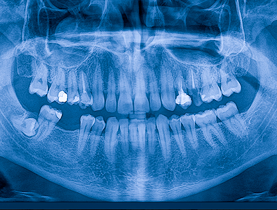

Our office has the capacity to take a complete series of diagnostic X-rays of your mouth to allow our dentists to identify oral problems that would be undetectable by a visual examination. We employ the use of digital panoramic X-ray and digital bitewing X-ray machines to obtain a complete picture of your teeth, gums and oral cavity.

Thanks to new digital technology, we can take X-rays of your mouth that use 90 percent less radiation that standard film X-rays. In addition, digital X-rays are immediately transmitted to a computer screen in our treatment room, so you don’t have to spend your valuable time waiting for your X-rays to be developed. Instead, you can see the images of your teeth instantly, and computer technology allows the X-rays to be enlarged, highlighted, inverted or even colorized, helping you and your dentist see hard-to-spot dental problems.